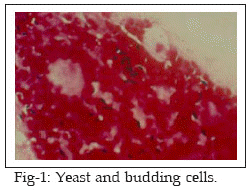

Fifteen patients attending at the Jahad and Razi Laboratories supposed to be suffering from disease were involved in this investigation. It included 11 female (73.3%) and 4 males (26.7%). The ages of the patients ranged between 4-30 years with a mean of 17 years. All patients had one or more of the aural symptoms (itching, otalgia, hearing loss). Secretion and pus were collected from the ear by two sterile cotton wool swabs. One swab was used for direct microscopy and other for culture examination. Direct examination of the samples was carried out by staining the smears with methylene blue and Gram techniques. Otomycosis was confirmed by the presence of aseptate mycelium, septate mycelium, Aspergillus conidia, fruiting bodies, yeast and pseudohyphae (Figs 1-4). The presence of fungal elements in stained smears was re-confirmed by fungal culture fungal colonies. Any kind of clinical materials, especially liquid samples (swabs, pus) should be examined as quickly as possible. Swabs did not require processing and were directly used for culture. Swabs were rolled and inoculated over the surface of Sabouraud’s Dextrose Agar with chloramphenicol (SC). Cultures were incubated at laboratory ambient (25-27°C) for 2-3 weeks, aerobically. Fungal isolates (moulds) were identified on the basis of colonial morphology and slide cultures. Yeast colonies, also detected by germ tube test, production of chlamydoconidia on corn meal agar and API 20 C AUX system.

Results